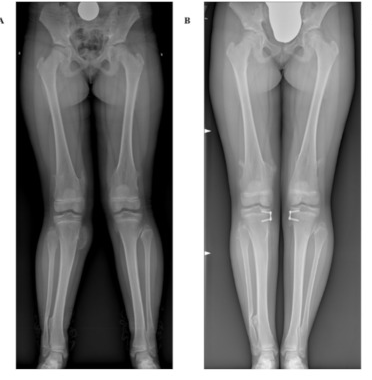

Un certo grado di varismo o di valgismo del ginocchio è considerato fisiologico durante l’età evolutiva. Un ginocchio varo è considerato entro certi limiti normale dai 12 ai 30 mesi circa mentre, in seguito, il ginocchio risulterà modicamente valgo sino ai 6-7 anni di età per poi solitamente correggersi autonomamente (Fig.1)

Qualora le deviazioni, idiopatiche o post-traumatiche, siano presenti in soggetti in crescita (in cui cioè è ancora presente attività della cartilagine di accrescimento o fisi) è possibile trattarle mediante un intervento chirurgico noto come epifisiodesi asim-metrica temporanea (Fig.2-3). Tale intervento sfrutta il potenziale di crescita residuo per “guidare” lo sviluppo favorendo la correzione del valgismo o del varismo. Ciò avviene mediante l’utilizzo di placchette lunghe pochi centimetri posizionate a cava-liere della/e fisi in grado di modulare l’accrescimento in tale sede. L’intervento pre-vede solo una piccola cicatrice, è descritta ampiamente una buona tollerabilità al do-lore grazie anche all’utilizzo di un’anestesia generale combinata con una loco-regionale del sito chirurgico.